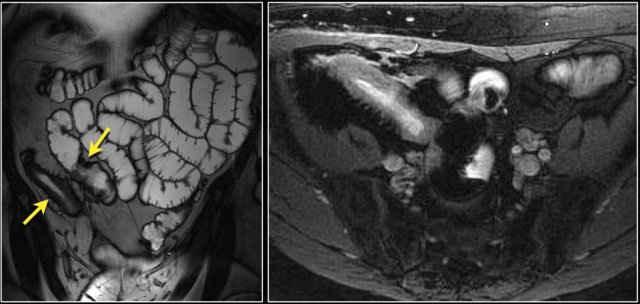

Here a patient with extensive wall thickening of the proximal jejunum with aneurysmatic dilatation.

On top of our differential diagnostic list would be a lymphoma, but this proved to be an adenocarcinoma.

Features that favour adenocarcinoma are fat stranding due to mesenteric fat infiltration and lymph node metastases.

In lymphoma fat stranding is uncommon, but lymph node metastases do occur and are usually more bulky.

The images show a short obstructing circular mass in the jejunum (yellow arrow) with enlarged lymph node (red arrow).

This proved to be an adenocarcinoma.

Post-contrast T1W-image with fatsat (left) and T2W-image (right) show an obstructing mass in the jejunum with shouldering (arrow).

There is prestenotic dilatation.

Top images show a circular mass in the proximal jejunum with FDG uptake (yellow arrows).

Lower MR-images show the same jejunal mass with shouldered borders and mesenteric lymphadenopathy (red arrows), consistent with adenocarcinoma.